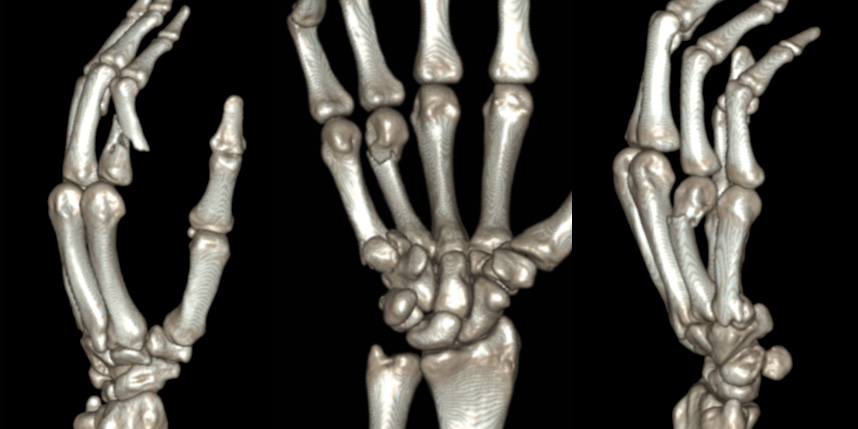

손목 골절

손가락 골절